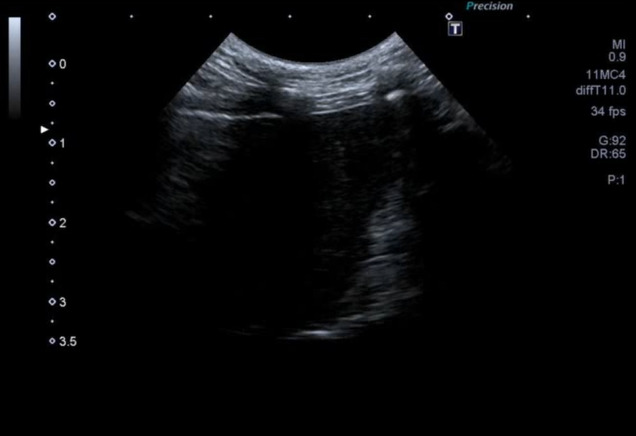

図3C 心原性肺水腫の猫における肺超音波画像

雑種猫、8歳5カ月齢、去勢雄、体重4.68kg。心疾患の管理中であったが、3日ほど投薬できておらず、かかりつけ医より紹介来院した。肺水腫によりB-lineの増加(white lung)が認められた。

特集 悩ましい猫の肺炎 vs. 肺水腫 vs. 肺腫瘍(塗木貴臣先生)図3Ⅽ